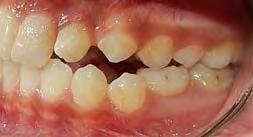

Se presenta una paciente de 17 años y 5 meses diagnosticada con clase I esquelética, hipodivergente, clase I molar y canina izquierda, clase II molar derecha y la clase canina derecha sin identificar debido al canino 13 retenido, mordida abierta en sector de laterales, overjet y overbite disminuidos, línea media dental superior desviada a la derecha y la inferior desviada a la izquierda, microdoncia de los incisivos 12 y 22. Objetivo: mantener el perfil facial, y las relaciones esqueléticas maxilomandibulares, realizar cirugía del 13, corrección de rotaciones dentales en el maxilar, mantener la clase I molar izquierda y obtener la clase I molar derecha, mantener la clase I canina izquierda, obtener clase I canina derecha, cerrar mordida abierta de sector de laterales, corrección del overjet y overbite, corrección de líneas medias dentales, manejo de Bolton, mejorar estado periodontal, lograr correcta intercuspidación, guía de desoclusión canina e incisiva y restauración de los dientes 12 y 22. Tratamiento: alineación, nivelación, tracción canina del 13, detallado y retención. Tiempo de tratamiento: 2 años y 9 meses.

Caso clínico

Se presenta una paciente de 13 años 5 meses con el motivo de consulta “es que no me baja el colmillo”. En los estudios extraorales se ve el perfil concavo y labios en contacto durante el reposo (Figura 1). En los estudios intraorales tenemos , clase I esquelética, con crecimiento hipodivergente (Figura 2), clase II molar derecha y clase I molar y canina izquierda, la clase canina derecha no determinada

Figura 1. Perfil, frente en reposo, sonrisa.

(ND), órgano dental (OD) 13 retenido, mordida abierta en sectores laterales, overjet de 3 mm y overbite de 10%, líneas medias dentales desviadas y microdoncia de OD 12 y 22.

Radiografía panorámica. Se ven 34 dientes (Figura 3), con el canino 13 retenido y los órganos denatrios 75 y 85 están próximos a ser exfoliados. Los segundos molares aún están terminando su formación y aparece el germen dentario de los terceros molares.

En la oclusal superior vemos la forma de la arcada que es oval con apiñamiento leve (Figura 4) y la inferior es cuadrada.